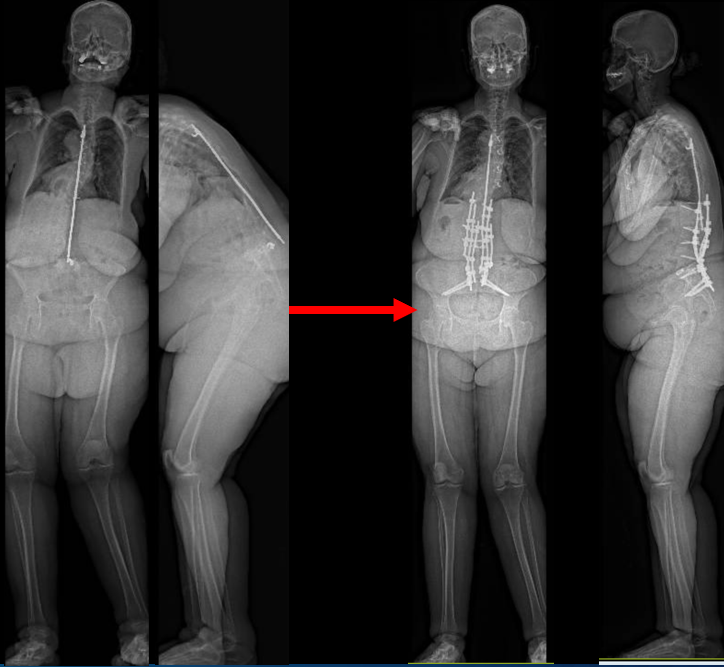

Severe malalignment case: Performed T12-S1/Pelvis posterior instrumentation, TLIF at L5-S1 & L5 PSO. No anterior approach on vascular team's advice. Patient now stands upright & grateful. #SpineSurgery #MedTwitter #scoliosis #flatback #HarringtonRods #ScoliosisWarrior

50s patient with severe malalignment. How would you treat this surgically? Nnee compensation in coronal and sagittal planes. Options: Multisegment instrumentation, TLIF/ALIF/OLIF, PSO, refer to another surgeon? Thoughts? #neurosurgery #spine #scoliosis #flatback #harringtonrods